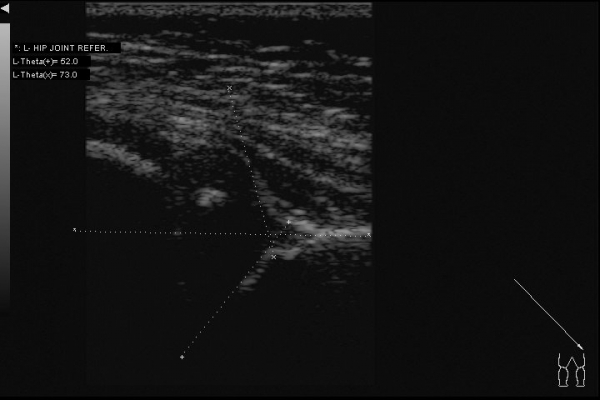

Доброго всем дня. Интересный случай сегодня: клинически у ребенка (2,5 месяца) все нормально -- отведение в полном объеме, ротация -- норма. Складки -- симметрия. Но!!! В анамнезе у мамы ребенка врожденный вывих бедра. Решил выполнить УЗИ:

Таким образом видим полное соответствие УЗИ картины -- рентгенограмме.